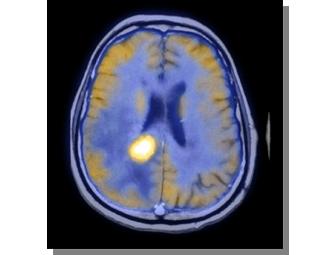

An extremely rare opportunity to spend the "day" with noted Chief of Nuclear Medicine and PET Imaging, David K. Shelton, MD. Dr. Shelton will personally lead you on a behind the scenes tour of UC Davis Medical Center. Whether brain scans or whole body imaging, he will show you cutting edge medical technology for diagnostics and treatment and talk to you about the future of medicine. Dr. Shelton is also professor of radiology and nuclear medicine at the University of California, Davis, School of Medicine and recently completed a "tour of duty" as Chief of Staff.

Dr. Shelton specializes in diagnostic radiology, including CT, MRI and percutaneous lung biopsies. He is studying cardiothoracic radiology, nuclear medicine, computer networking systems in nuclear radiology, functional cardiac protocols, and tumor work-up staging of functional imaging. Dr. Shelton pioneered the development of transesophageal echocardiography, and has presented nationally on osteoporosis, skeletal metastases in lung cancer patients, thyroid carcinoma, cardiovascular MRI and SPECT. He also has authored eight radiology textbook chapters and reviews for the Western Journal of Medicine and the Journal of Thoracic Imaging.